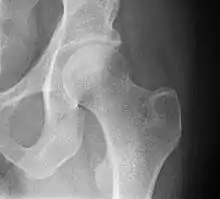

X-ray of a normal hip joint.

Functional anatomy

The hip joint, is a ball-and-socket joint. The femur connects at the acetabulum of the pelvis and projects laterally before angling medially and inferiorly to form the knee. Although this joint has three degrees of freedom, it is still stable due to the interaction of ligaments and cartilage. The labrum lines the circumference of the acetabulum to provide stability and shock absorption. Articular cartilage covers the concave area of acetabulum, providing more stability and shock absorption. Surrounding the entire joint itself is a capsule secured by the tendon of the psoas muscle and three ligaments. The iliofemoral, or Y, ligament is located anteriorly and serves to prevent hip hyperextension. The pubofemoral ligament is located anteriorly just underneath the iliofemoral ligament and serves primarily to resist abduction, extension, and some external rotation. Finally the ischiofemoral ligament on the posterior side of the capsule resists extension, adduction, and internal rotation. When considering the biomechanics of hip fractures, it is important to examine the mechanical loads the hip experiences during low energy falls.